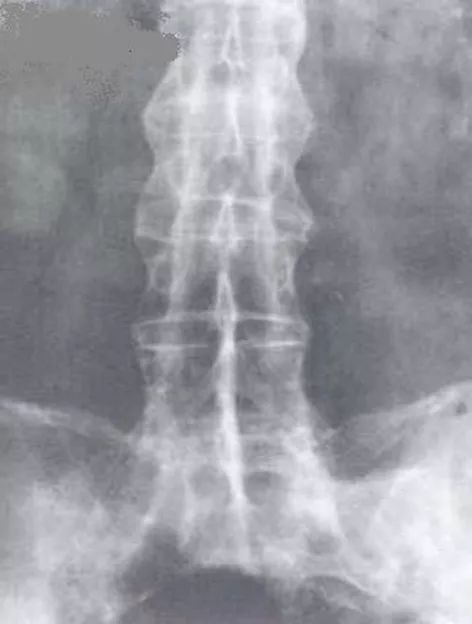

姑娘|姑娘订了婚,男友总喊腰疼,去医院一查……想退彩礼!

在一起后男友却总说腰疼

不得已去医院检查

结果……

现在打算退彩礼、退定金